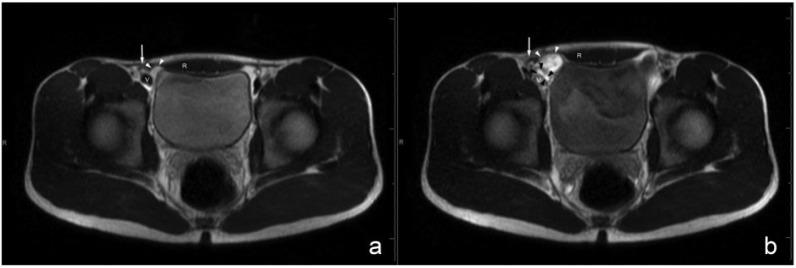

Ultrasound was positive for hernia with movement of bowel, bladder, or omental tissue anterior to the inferior epigastric vessels during Valsalva maneuver. The 47-patient symptomatic study group included 41 patients with direct inguinal hernias, 1 with indirect inguinal hernia, and 5 with negative ultrasound. Of 42 patients with hernia, 39 significantly improved with herniorrhaphy, 2 failed to improve after surgery and were diagnosed with adductor longus tears, and 1 improved with physical therapy. Five patients with negative ultrasound underwent magnetic resonance imaging and were diagnosed with hip labral tear or osteitis pubis. The 41-patient asymptomatic control group included 3 patients with direct inguinal hernias, 2 with indirect inguinal hernias, and 3 with femoral hernias.

在瓦尔萨尔瓦动作期间,超声显示疝内容物(肠管、膀胱或网膜组织)在腹壁下血管前方移动,提示疝存在。47例有症状的研究组患者中,41例为腹股沟直疝,1例为腹股沟斜疝,5例超声检查结果为阴性。42例疝患者中,39例疝修补术后明显改善,2例术后未改善,诊断为内收长肌撕裂,1例经物理治疗后改善。5例超声检查结果为阴性的患者接受磁共振成像检查,诊断为髋关节盂唇撕裂或耻骨炎。41例无症状对照组患者中,3例为腹股沟直疝,2例为腹股沟斜疝,3例为股疝。